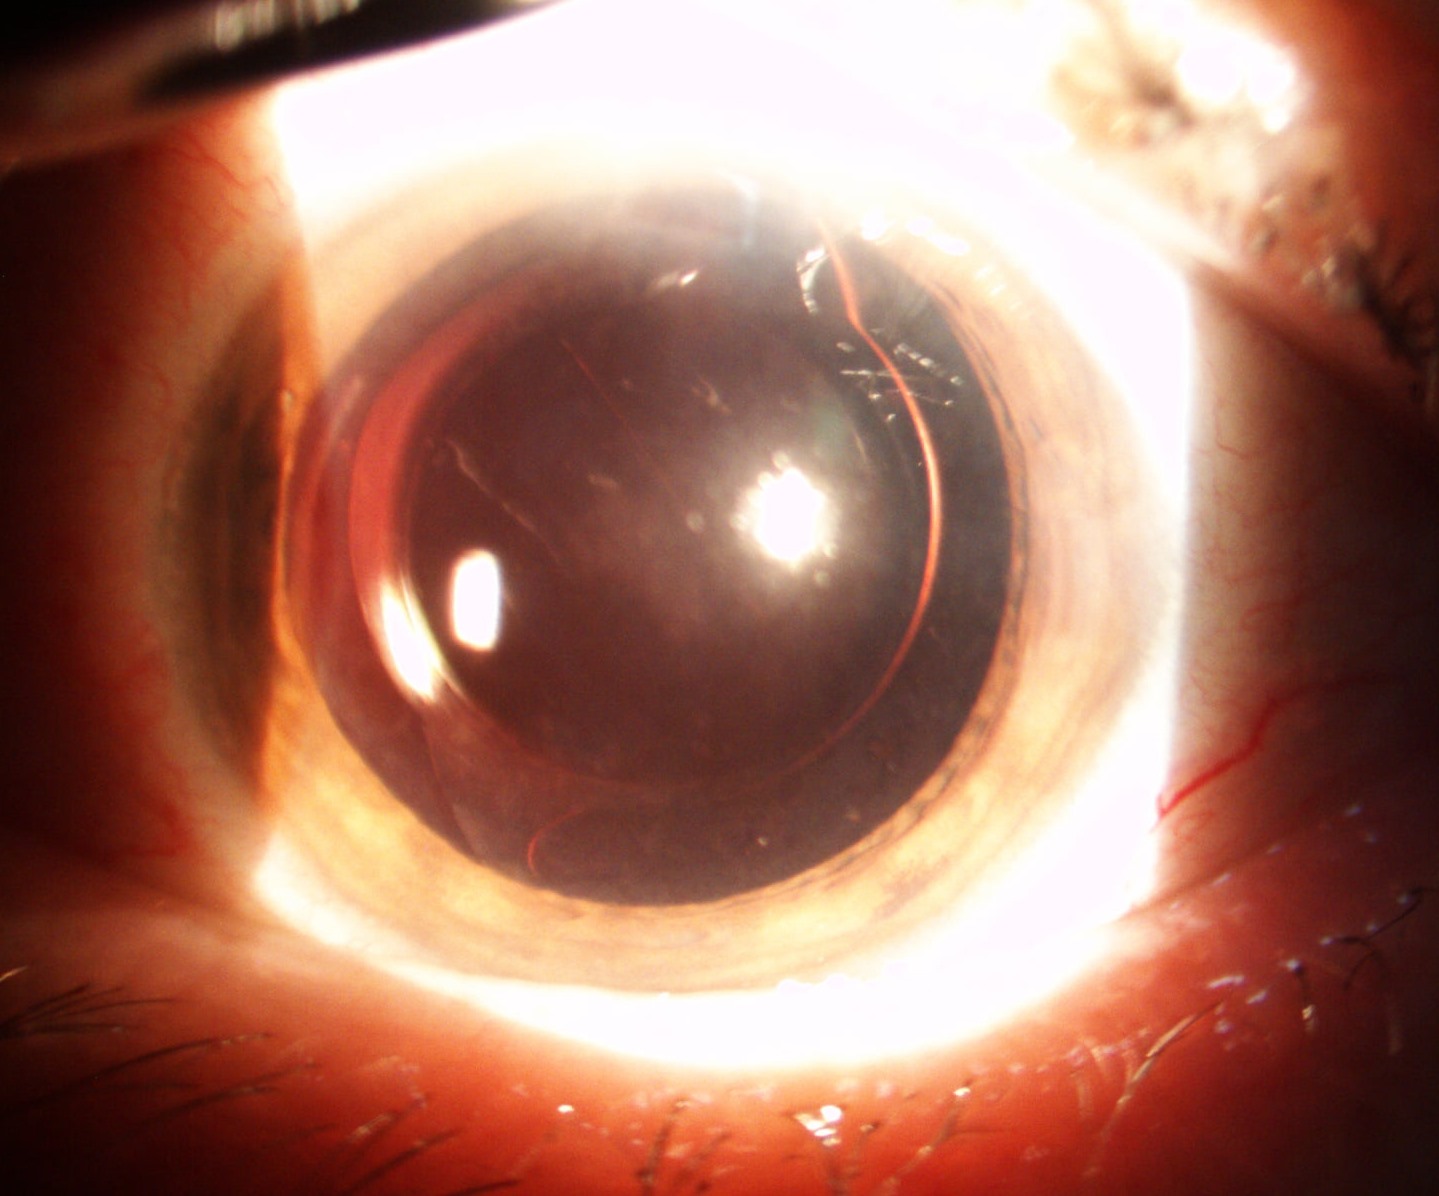

Mai jos, fotografii ale mai multor pacienti de-ai nostri cu Corneea Guttatta în faze medii, sau chiar avansate, la care am efectuat doar operația de cataractă, în urma căreia corneea a „supraviețuit” cu brio și nu a mai fost nevoie – cel puțin până acum – de un trasplant de cornee.